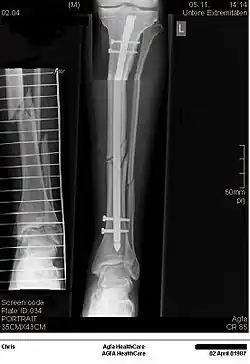

Komplette Unterarmschaft-fraktur beim Kind mit deutlicher Knickbildung -

Versorgung derselben Fraktur mit je einem Prevot-Nagel (ESIN) in Radius und Ulna